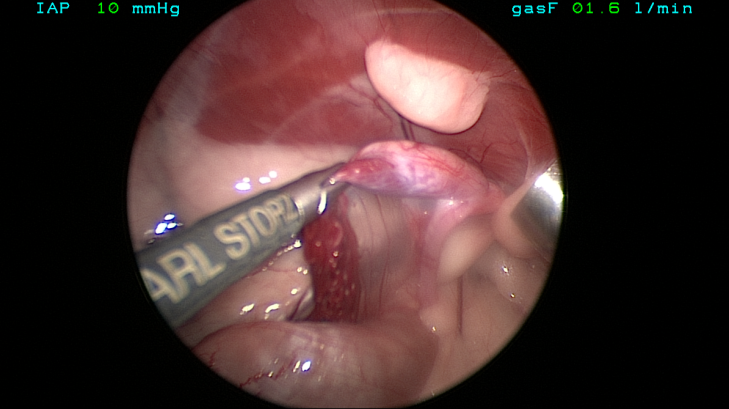

The episiotomy was then closed routinely and laparoscopic gonadectomy performed. Both gonads were grossly consistent with testes (Fig 7) and so Sally was suspected to be a genetic male.

True hermaphroditism would require both testicular and ovarian tissue to be present in the same individual and this was clearly not the case here. “Pseudohermaphroditism” is also termed “Intersex” and is caused by intrauterine failure of the SRY gene to achieve full male differentiation. A “Male Intersex” is a dog that has male gonads (testes) but external genitalia resembling those of females. Although full karyotype analysis would be required to be sure of Delilah’s genetics, histopathology of the gonads confirmed that they were testes and so a clinical diagnosis of “Male Intersex” is appropriate for this case.